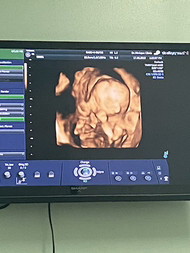

ซาวด์ท้อง4มิติ

เราซาวด์ 4 มิติ ตั้งแต่ 20w 24w และ 34w เราหมอส่งซาวด์นะคะ ไม่ได้ไปหาซาวด์เอง

ของบ้านนี้เพิ่งซาวด์มาเมื่อวานค่ะ มาตัดสินใจซาวด์ตอน 36 วีค😂

กี่weekถึงซาว์น4มิติเห็นชัดคะ

กี่weekซาว์นเห็นชัดคะ

26 วีค5วันค่ะ